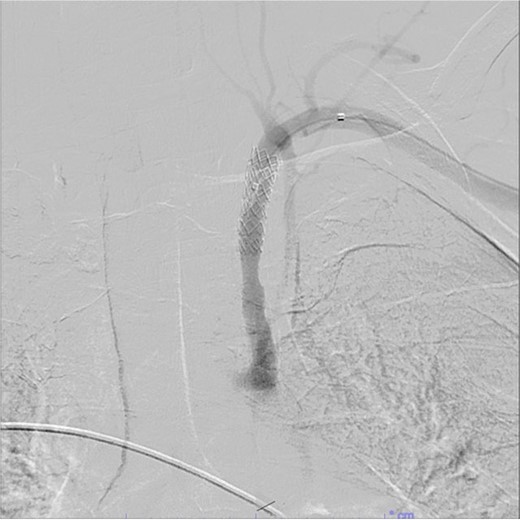

A 67-year-old male with a medical history significant for hypertension, diabetes, coronary artery disease, carotid artery stenosis, osteoarthritis, and 50 pack-year smoking history presented initially to an orthopedic surgery office for evaluation of left shoulder pain after exercising. The patient was found to have an underlying rotator cuff injury and was subsequently treated with cortisone injection. The patient subsequently developed septic arthritis, ultimately requiring incision and drainage of the abscess and resection of the sternoclavicular joint, partial first rib, and partial clavicle. The patient required multiple washouts and debridement procedures, ultimately leading to septic shock and bacteremia requiring close observation in the surgical intensive care unit. A computed tomography angiogram (CTA) of chest was performed at the time and revealed a subcentimeter penetrating ulcer, arising from the proximal left subclavian artery likely secondary to surgical trauma, which was observed nonoperatively given the patient critical status in the intensive care unit (ICU) (Figs 1 and 2). During the ICU course, the patient developed left upper extremity swelling A left upper extremity duplex ultrasound subsequently revealed a nonocclusive deep vein thrombosis of the subclavian vein and also showed resolution of a pseudoaneurysm (PSA) of the subclavian artery. The patient was started on anticoagulation at this time for a deep vein thrombosis (DVT). The patient was ultimately discharged upon resolution of his acute infection to a rehabilitation facility. During the third-month follow-up office visit, the fistulous connection between the subclavian artery and vein was found incidentally on left upper extremity duplex ultrasound (Fig. 3). Physical exam of the patient was otherwise unremarkable with palpable upper extremity pulses and the patient did not appear to have any symptoms related to the fistula including upper extremity swelling or open wounds. The patient was scheduled for an elective repair of the fistula via endovascular stent graft placement. The patient was brought to the operating room, and the radial artery was accessed with a micropuncture device. Radial artery access was our choice to intervene given the location of fistula. When left upper extremity angiography was performed, it revealed a blush of contrast from proximal subclavian artery, revealing a small fistula between subclavian artery and subclavian vein (Fig. 4). Subsequently, a 6 × 29 mm balloon-mounted stent graft was used to cover the fistula. Completion angiography was performed showing adequate seal with resolution of the fistula (Fig. 5). The patient tolerated the procedure well and was subsequently discharged from the hospital the same day. He was started on antiplatelet therapy post-operatively and continued oral anticoagulation for the DVT. The patient was seen in the office at 3-month follow-up, where a repeat duplex ultrasound revealed normal waveforms and velocities throughout the left arm. He was also seen in the office recently, and he is doing well with no new complaints.

Demonstration of covered stent placement and resolution of the fistulous connection.